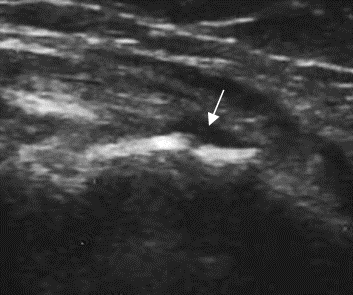

Fig 49 B. Ruptura parcial.

Ecografía en vista longitudinal. Solución de continuidad en fibras, sobre el origen conjunto de

los tendones extensores sobr el epicóndilo lateral, por ruptura parcial.